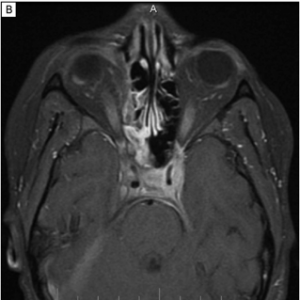

Imaging can aid in diagnosis, especially in cases of orbital soft tissue or EOM involvement, which are better appreciated on orbital imaging. Imaging techniques include CT or MRI of the orbits, and fluorodeoxyglucose (FDG)-PET/CT scan. MRI will demonstrate isointensity on T1-weighted lesions, hypointensity on T2-weighted lesions, and homogenous gadolinium enhancing lesions.[42] FDG-PET scan can be used for systemic evaluation in IgG4-RD, as it can locate distant and/or clinically silent lesions.[43] There are currently no guidelines on how often FDG-PET/CT should be performed.